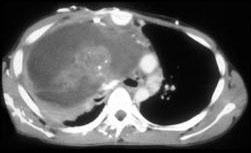

问题 男,37岁,咳嗽,咯血2月余,偶尔咳出钙化物,请结合影像学检查,选出最可能的诊断 ( )

选项 A、淋巴管瘤 B、淋巴瘤 C、肺癌 D、胸腺瘤 E、畸胎瘤

答案 E